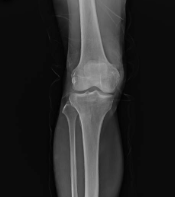

1. 관절염과 통증 완화

글루코사민의 효능 중 가장 잘 알려진 것은 골관절염과 관련된 통증을 줄이는 능력입니다. 글루코사민은 연골의 구성 성분으로 작용하여, 연골이 마모되는 것을 늦추고 기존 연골의 회복을 도와 통증과 뻣뻣함을 감소시킵니다. 이는 연골 밑의 뼈가 서로 마찰되는 것을 방지하여, 관절의 유연성을 향상시키고 일상 활동 시 통증을 감소시키는 데 도움을 줍니다.

5. 뼈 건강 강화

글루코사민은 뼈의 건강을 유지하는 데 중요한 역할을 합니다. 뼈 조직의 회복을 지원하고 골밀도를 강화하여, 골다공증과 같은 뼈 관련 질환의 위험을 줄이는 데 도움을 줄 수 있습니다.